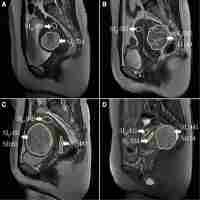

| Abstract | BACKGROUND Estimating pharmacological efficacy is important when selecting conservative treatment of uterine leiomyoma. Hence, the ability of magnetic resonance (MR) imaging to predict gonadotrophin-releasing hormone (GnRH) analogue efficacy was investigated. METHODS A total of 85 lesions was studied in 40 patients who were clinically diagnosed as having uterine leiomyoma and treated with GnRH analogue for 24 weeks. To evaluate changes in lesion size, T2-weighted and gadopentetate-dimeglumine (Gd-DTPA)-enhanced, T1-weighted MR images were obtained within 2 weeks before, and immediately after termination of, GnRH analogue treatment. RESULTS An average 46.3% size reduction was observed in 45 lesions (52.9%); these were seen as low signal intensity on T2-weighted images and enhanced by Gd-DTPA. Also, an average 44.7% size reduction was observed in lesions enhanced by Gd-DTPA, irrespective of signal intensity findings on T2-weighted images. The average size reduction of unenhanced lesions was only 17.8%, and significantly different from enhanced lesions (P < 0.001). The prediction of efficacy was difficult in those lesions not enhanced. CONCLUSIONS It is considered that evaluation of MR signal intensities, and the presence or absence of Gd-DTPA enhancement, would predict treatment efficacy before GnRH analogue administration. |